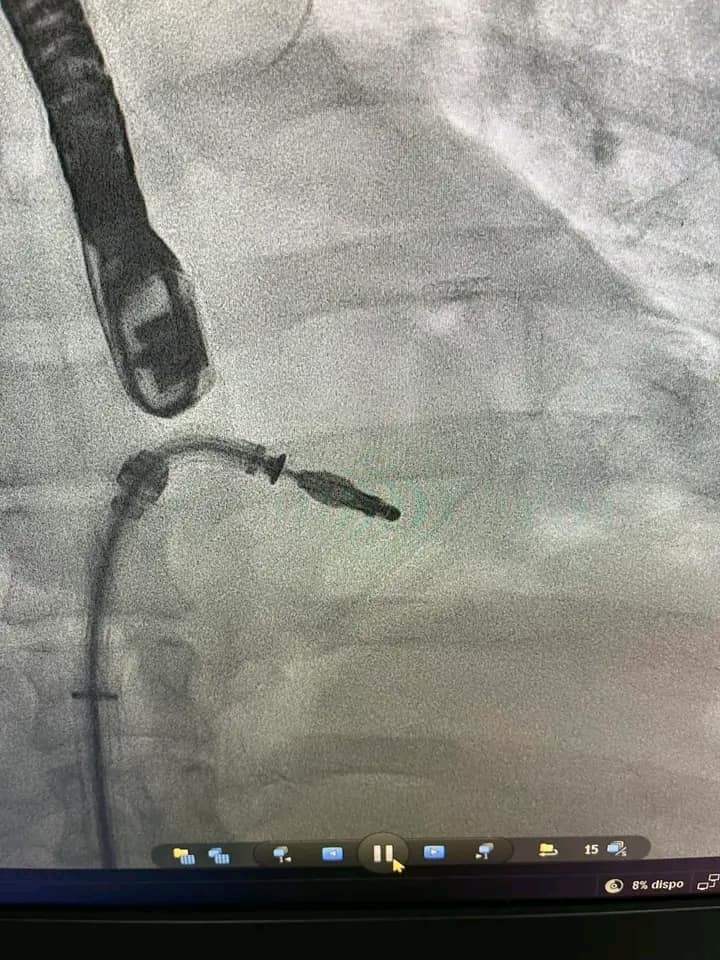

في نجاح هو الاول من نوعه في افريقيا تمكن فريق طبي تونسي متعدد الاختصاصات بالمستشفى العسكري بتونس من اجراء اول تطبيق طبي MITRACLIP.

وعملية MITRACLIP هو أحد العلاجات الموصى بها في حالة القصور التاجي ، ويسمى أيضًا الإصلاح التاجي عن طريق الجلد المخصص للمرضى الذين تشكل عملية القلب المفتوح خطرًا كبيرًا عليهم.